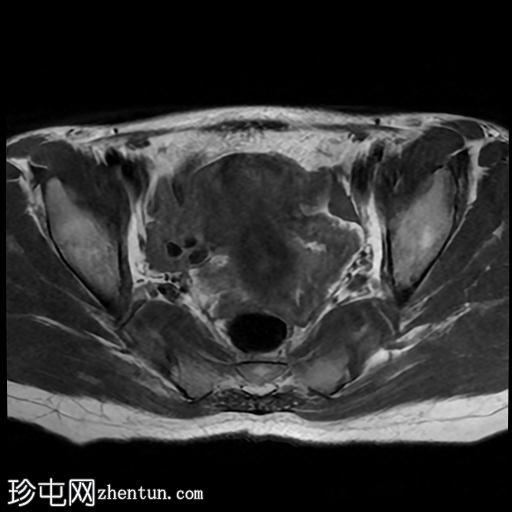

该宫颈癌体积较大,局部晚期,大小为22 x 40 x 42 mm,起源于宫颈左后外侧壁,向下延伸至阴道上三分之一处,位于宫颈中后外侧壁。

病变还累及左侧前外侧的宫旁组织。

影像学检查结果提示,根据 FIGO 分期系统,该患者为宫颈癌 IIIC1 期。

宫颈肿块活检的组织病理学报告显示为宫颈鳞状细胞癌,具体来说是角化型。